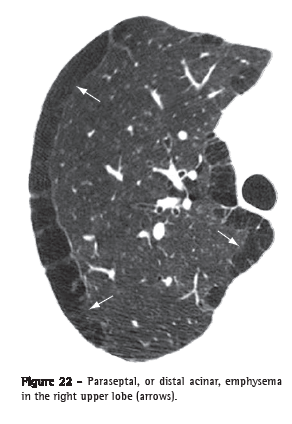

Paraseptal, or distal acinar, emphysema (enfisema parasseptal/acinar distal)Paraseptal emphysema affects predominantly the distal alveoli and their ducts and sacs. It is characteristically delimited by any pleural surface or interlobular septa. On CT scans, it is characterized by areas of low attenuation in the subpleural and peribronchovascular regions, separated by intact interlobular septum (Figure 22).(37,38) It is sometimes associated with bullae.